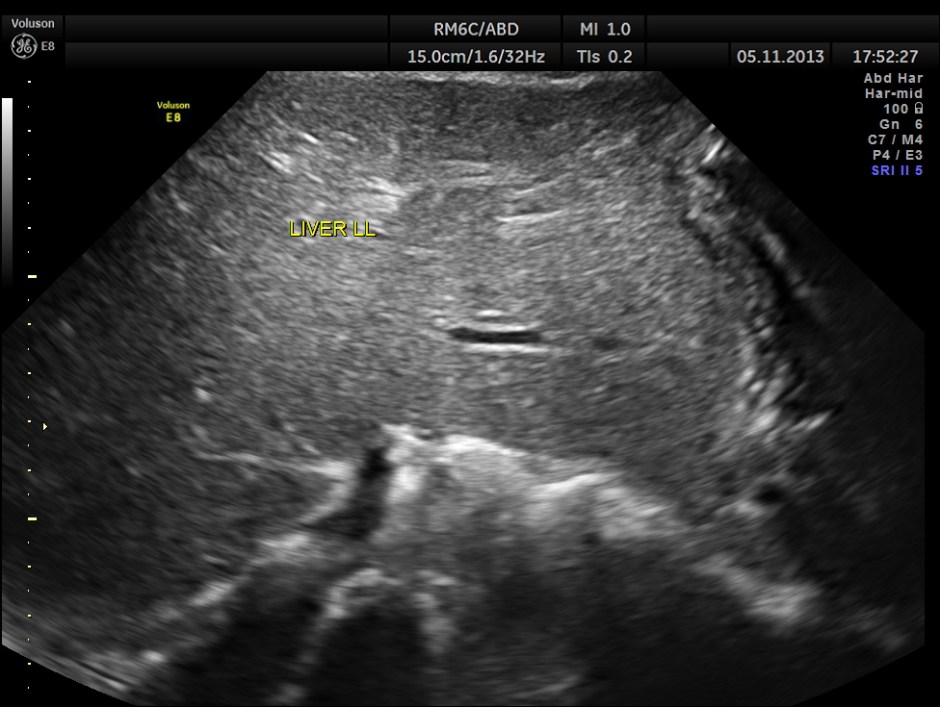

The left lobe of the liver appears to be normal.